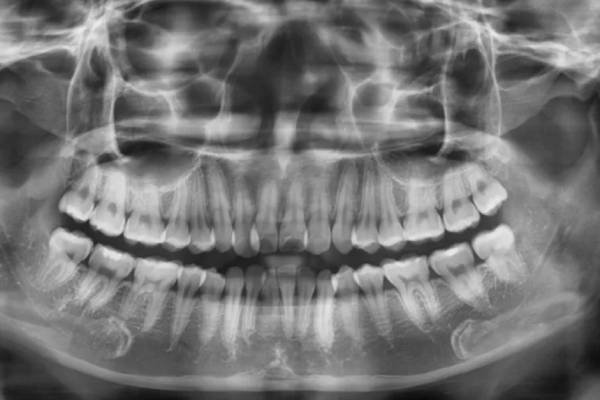

Nhổ răng khôn hiện nay được hỗ trợ bởi máy cắt xương siêu âm, X-quang 3D và công nghệ gây tê kỹ thuật số. Bác sĩ xác định chính xác vị trí chân răng và dây thần kinh trước khi thao tác. Nhờ vậy, thời gian nhổ được rút ngắn và người bệnh gần như không cảm thấy đau.

Một số ít trường hợp răng khôn mọc sát dây thần kinh hàm dưới hoặc ăn sâu vào xoang hàm trên. Khi đó, việc nhổ cần bác sĩ chuyên khoa răng hàm mặt thực hiện. Nếu thao tác sai, có thể gây tê môi, tê cằm hoặc chảy máu nhiều. Tuy nhiên, các biến chứng này rất hiếm, và đa phần là tạm thời.

Với công nghệ X-quang kỹ thuật số hiện nay, bác sĩ có thể tiên lượng chính xác trước khi nhổ để tránh mọi rủi ro.